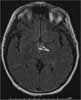

An MRI scan of the brain obtained as part of the workup for ataxia showed mammillary body necrosis (arrows), consistent with Wernicke encephalopathy.

Acute Wernicke encephalopathy is associated with mammillary body hemorrhage, whereas the chronic state is characterized by atrophy of the mammillary bodies. These features can be detected by MRI.